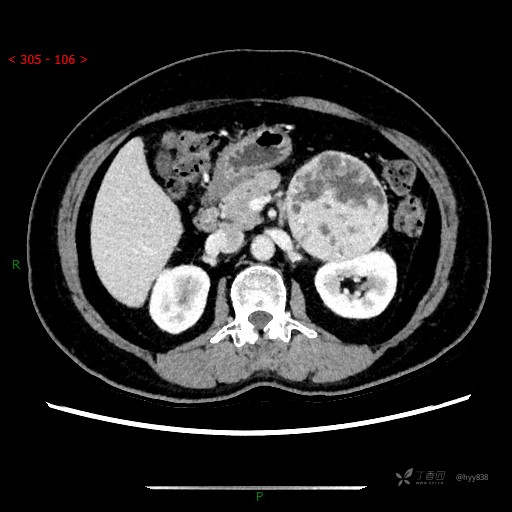

增强静脉期